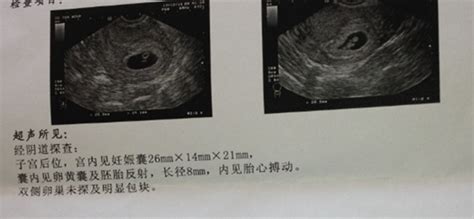

怀孕八个月B超结果如下:双顶径80mm.胎心率132次/分,股骨长59mm,羊水深约61mm,内透声好。胎盘附于子宫前壁,厚约28mm,绒毛板轻度起伏。这样正常吗,知不知道有几斤?谢谢